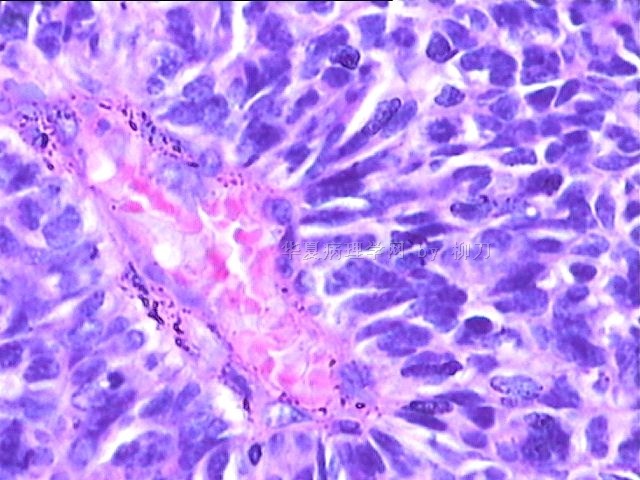

女,34y,头痛一月,右额叶占位:5*5*4cm。囊性区域,4cm。大体:3.5x3x1cm灰白间暗褐色组织一堆,质嫩。临床诊断1:胶质瘤,2:血管母细胞瘤。

同意胶质母细胞瘤。细胞异型、坏死、核分裂、血管内皮肿胀增生均可见到。

This is certainly a WHO grade IV malignant neoplasm. While most likely a glioblastoma, I would carefully rule out PNET by staining for GFAP and neuronal markers such as synaptophysin, NeuN and NSE. Rarely, PNET may shows marked pleomorphism and indistinguishable from glioblastoma on HE stain.

同意马老师的意见,该肿瘤从形态及年龄来看考虑PNET或GBM,须标记Syn、NSE、S-100、NeuN和GFAP来鉴别。

结合图片细胞形态特点考虑胶质母细胞瘤,组化标记排除其他